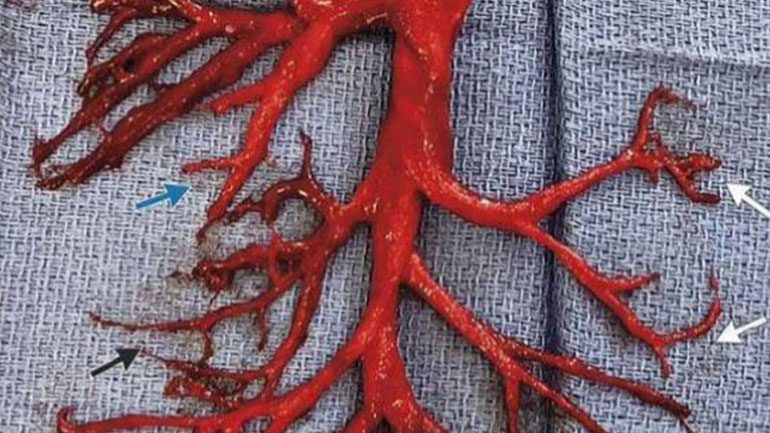

Η παραπάνω εικόνα ενός ανέπαφου θρόμβου αίματος πάρθηκε από έναν ασθενή το 2018 (πριν από την εμφάνιση του ιού SARS-CoV-2 στα τέλη του 2019), ο οποίος ύστερα από έντονο βήχα, απέβαλε έναν άθικτο θρόμβο (ο οποίος μοιάζει με κόκκινο κοράλλι ή ρίζες δέντρων). Η εικόνα είναι πραγματική.

«Ο 36χρονος ασθενής εισήχθη στη ΜΕΘ με αιφνίδια έξαρση χρόνιας καρδιακής ανεπάρκειας. Μετά την τοποθέτηση μιας συσκευής κοιλιακής υποβοήθησης και την έναρξη της αντιπηκτικής θεραπείας, αναπτύχθηκε αιμόπτυση και ύστερα από έντονο βήχα απέβαλε ένα κομμάτι του δεξιού βρογχικού δέντρου».

[Δηλαδή, στην κυριολεξία «έβηξε» μια ολόκληρο τμήμα των αγγειακών οδών ενός πνεύμονα, στο οποίο είχε σχηματιστεί ένας μεγάλος θρόμβος αίματος].

Σύμφωνα με το σχετικό ειδησεογραφικό ρεπορτάζ: «Οι γιατροί που εργάζονταν στο νοσοκομείο είπαν ότι ο άνδρας ένιωσε καλύτερα αμέσως μετά την αποβολή του θρόμβου με τον βήχα…».

Η συγκεκριμένη φωτογραφία, αν και δεν προήλθε από κάποιο θύμα του «εμβολίου»-Covid, αποτελεί μια καλή απεικόνιση του τι μπορεί να συμβαίνει στο σώμα κάποιων από εκείνους που κάνουν το «εμβόλιο»-COVID. Το «εμβόλιο» επηρεάζει το σύστημα της πήξης του αίματος και –σε μερικούς ανθρώπους–προκαλεί, ταχεία πήξη του αίματος, ακόμη και όταν ρέει μέσω των αρτηριών.

Οι θρόμβοι του αρτηριακού αίματος που προκαλούνται από τα «εμβόλια» – COVID σπανίως μοιάζουν με τον μεγάλο θρόμβο «κοραλιού» που φαίνεται στην παραπάνω φωτογραφία, επειδή αυτός ο θρόμβος αίματος λήφθηκε από τους βρογχικούς αεραγωγούς του πνεύμονα, οι οποίοι για κάποιο λόγο είχαν γεμίσει με αίμα που, στη συνέχεια, έπηξε.